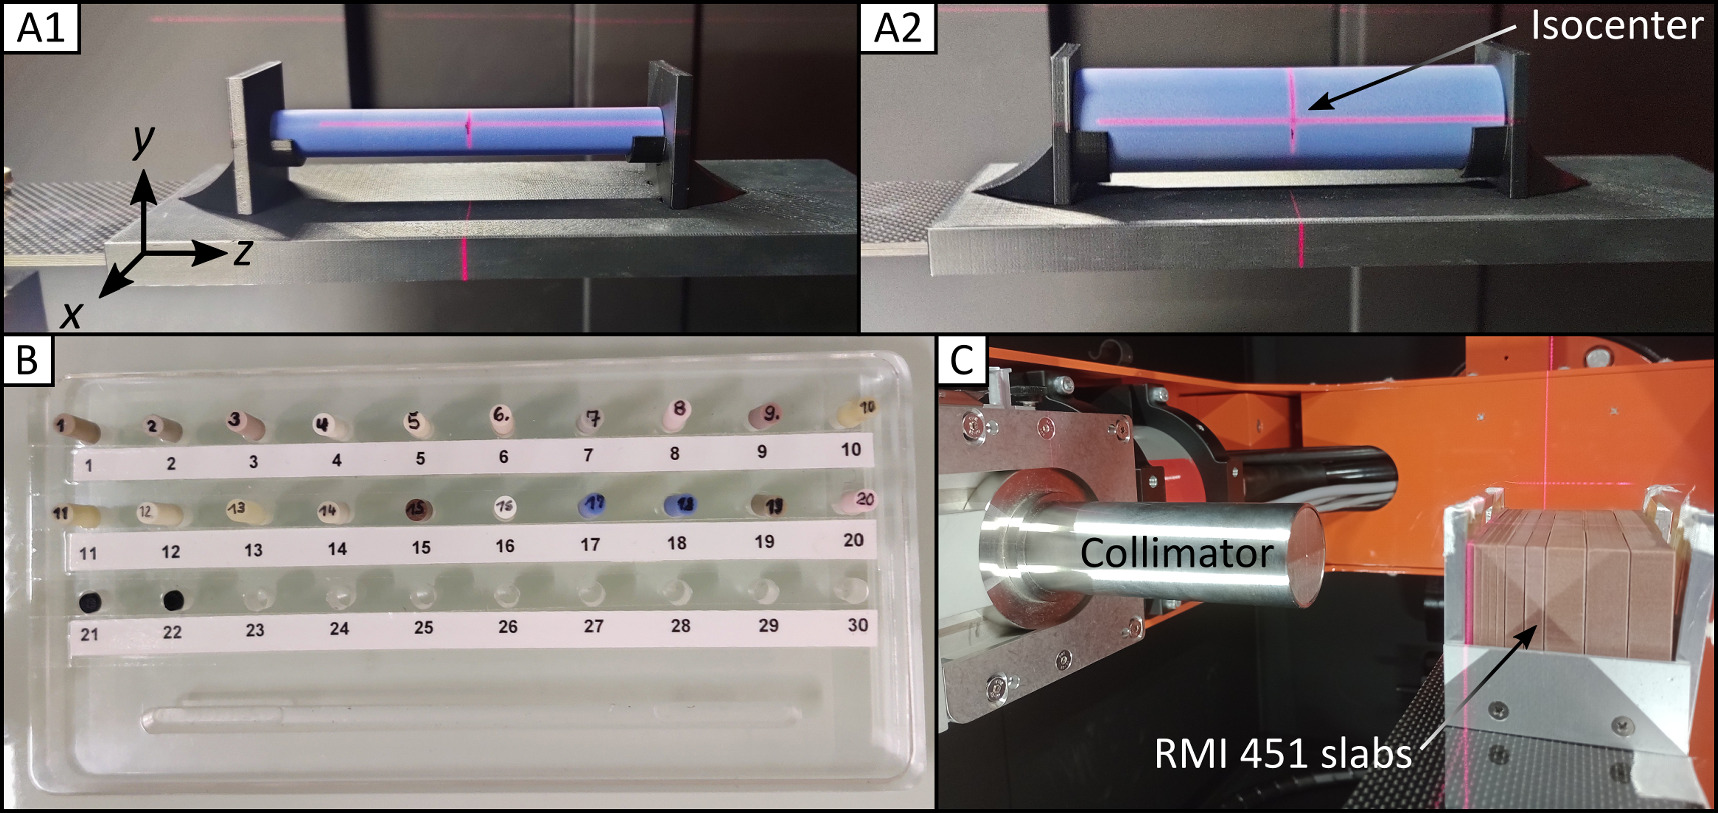

2.1. Beamline setup

The SmART+ IB stands on rollers in the experimental area of the UPTD and can be placed square to a horizontal beamline providing a static proton pencil beam. The correct position of the SmART+ IB is ensured every time with millimeter precision by measuring the distance of the device to the proton beam exit as well as to the wall using a digital laser measure (type GLM 50 C, Robert Bosch Power Tools GmbH, Leinfelden-Echterdingen, Germany). The device (figure 1) is equipped with a specially designed window on the back at the height of the beam pipe, allowing for integration of a proton beam. The fully shielded device features a bifocal 225 kV x-ray tube (internal filtration: 0.8 mm Beryllium) with filter slide and collimator mount, a flat panel detector (0.2 mm resolution, total area 20 × 20 cm2), a 360° rotating gantry with 30.5 cm source-axis distance, and an X–Y–Z animal stage, allowing for CBCT imaging and photon irradiation using nine different fixed nozzle collimators (circular with diameters 1 mm, 3.5 mm, 5 mm, 10 mm, 15 mm, 25 mm and square 10 × 10 mm2, 20 × 20 mm2, 40 × 40 mm2). A supplied 2 mm thick aluminum filter is inserted for CBCT imaging, and a 0.5 mm thick copper filter is used for photon irradiation to prevent beam hardening. For proton irradiation, a 45.82 mm thick polymethylmethacrylat (PMMA) range shifter with a water equivalent thickness (WET) of 53.16 mm for 90 MeV was utilized to be consistent with previous small animal brain studies (Suckert et al 2020, 2021b). The range shifter was attached to an aluminum collimator with a 3 mm diameter aperture placed on two linear stages (LTM80P-75-HSM, LTM80P-150-HSM, OWIS GmbH, Staufen im Breisgau, Germany) on the animal stage for lateral displacement. Monte Carlo (MC) simulations (FLUKA2020 Version 2c.6, (Fasso et al 2005, Battistoni et al 2015)) were performed to determine the optimal position of the collimator and range shifter in the beam path to minimize dose contributions by scattered protons and secondary neutrons and thus protect the shielded device, the flat panel detector and electronics (figure 2). The PRECISIOn default settings were used and the dose and fluence distributions were obtained by applying the USRBIN scorer. Based on the simulations, the collimator and range shifter were positioned as close as possible to the animal box, resulting in proton and neutron fluence as well as absorbed doses at both the flat panel detector and the SmART+ IB wall being several orders of magnitude lower than those of the central beam. The shutter of the flat panel detector efficiently protects it from scattered protons, but is transparent to neutrons. However, the secondary neutrons are emitted in a forward cone, so that the neutron exposure in the direction of the detector is expected to be relatively low. For irradiation with high doses, additional neutron shielding, preferably consisting of hydrogen-rich materials like polyethylene plates, could be placed on top of the steel shutter to minimize long-term damage to the flat panel detector. Two adapters fitting the animal stage were 3D printed from acrylonitrile butadiene styrene (ABS) for stable repositioning of phantoms used for CBCT imaging (figures 3(A1)/(A2)).

Standard image High-resolution imageFigure 3. Phantoms for CBCT and photon beam characterization. Cylindrical head (A1) and body (A2) phantoms on the 3D printed adapter at the animal stage placed at SmART+ IB isocenter. (B) Used inserts numbered with 1–22 made from tissue-equivalent materials, which can be placed inside the phantoms. (C) Setup for measuring depth dose and lateral profiles of the photon beam with a  collimator in horizontal position (irradiation position in mice) using EBT3 films between RMI451 water slabs of thickness 2 mm, 5 mm and 10 mm.

collimator in horizontal position (irradiation position in mice) using EBT3 films between RMI451 water slabs of thickness 2 mm, 5 mm and 10 mm.

For image quality evaluation, two cylindrical phantoms (head: A1, body: A2 in figure 3) made of solid water (Solid Water HE, Gammex-RMI GmbH, Gieen, Germany) with diameters of 15 mm and 30 mm, respectively, and a length of 120 mm incorporating a central 5 mm diameter drilled hole were employed. The tissue-equivalent materials for the phantoms are shown in figure 3(B) (see section 2.6). The CBCT homogeneity within these phantoms, the contrast-to-noise ratio (CNR), and the visibility of notable skull structures of a deceased laboratory mouse were examined. For all image quality evaluations, one CBCT was acquired for each imaging protocol. The homogeneity was investigated in all three spatial directions x, y, and z, inside the phantoms, which were precisely positioned at the SmART+ IB isocenter using a system of room lasers inside SmART+ IB. The CNR was determined based on the CBCT values of the same solid water phantom  and the surrounding air

2.3. Photon beam characterization

To characterize the photon beam, depth dose profiles and lateral profiles were acquired for seven collimators at the SmART+ IB's isocenter operating at 200 kV, 20 mA, with the 0.5 mm copper filter (half-value layer (HVL): 1.03 mm Cu). Figure 3(C) shows the setup for the beam measurements, in which GafChromic EBT3 films (Ashland Inc., Wilmington, Delaware, USA) were placed inside a solid water slab phantom (type 451, Gammex-RMI GmbH, Gieen, Germany) at different depths for both 20 s and 80 s exposures.

2.6. Hounsfield lookup table

For a precise prediction of proton ranges on basis of CBCT images of SmART+ IB, a device and system-specific HLUT needs to be created defining the relationship between HU values and proton stopping power ratio (SPR) relative to water. To create this HLUT, 19 different cylindrical tissue-equivalent inserts (5 mm diameter, 30 mm length) were placed inside the head and body phantoms (see figures 3(A)/(B)). The assignment of the materials and their material properties can be found in the supplementary materials in table S1. For each phantom, a CBCT was taken with the best imaging protocol, and the SPRs were extracted from the work of Peters (2022). This empirical method for determining the HLUT was subsequently validated by the stoichiometric method of Schneider et al (1996) including 71 human tissues as well as the 19 materials. The influence of the animal box on the HLUT due to the shifted CT numbers was also assessed.